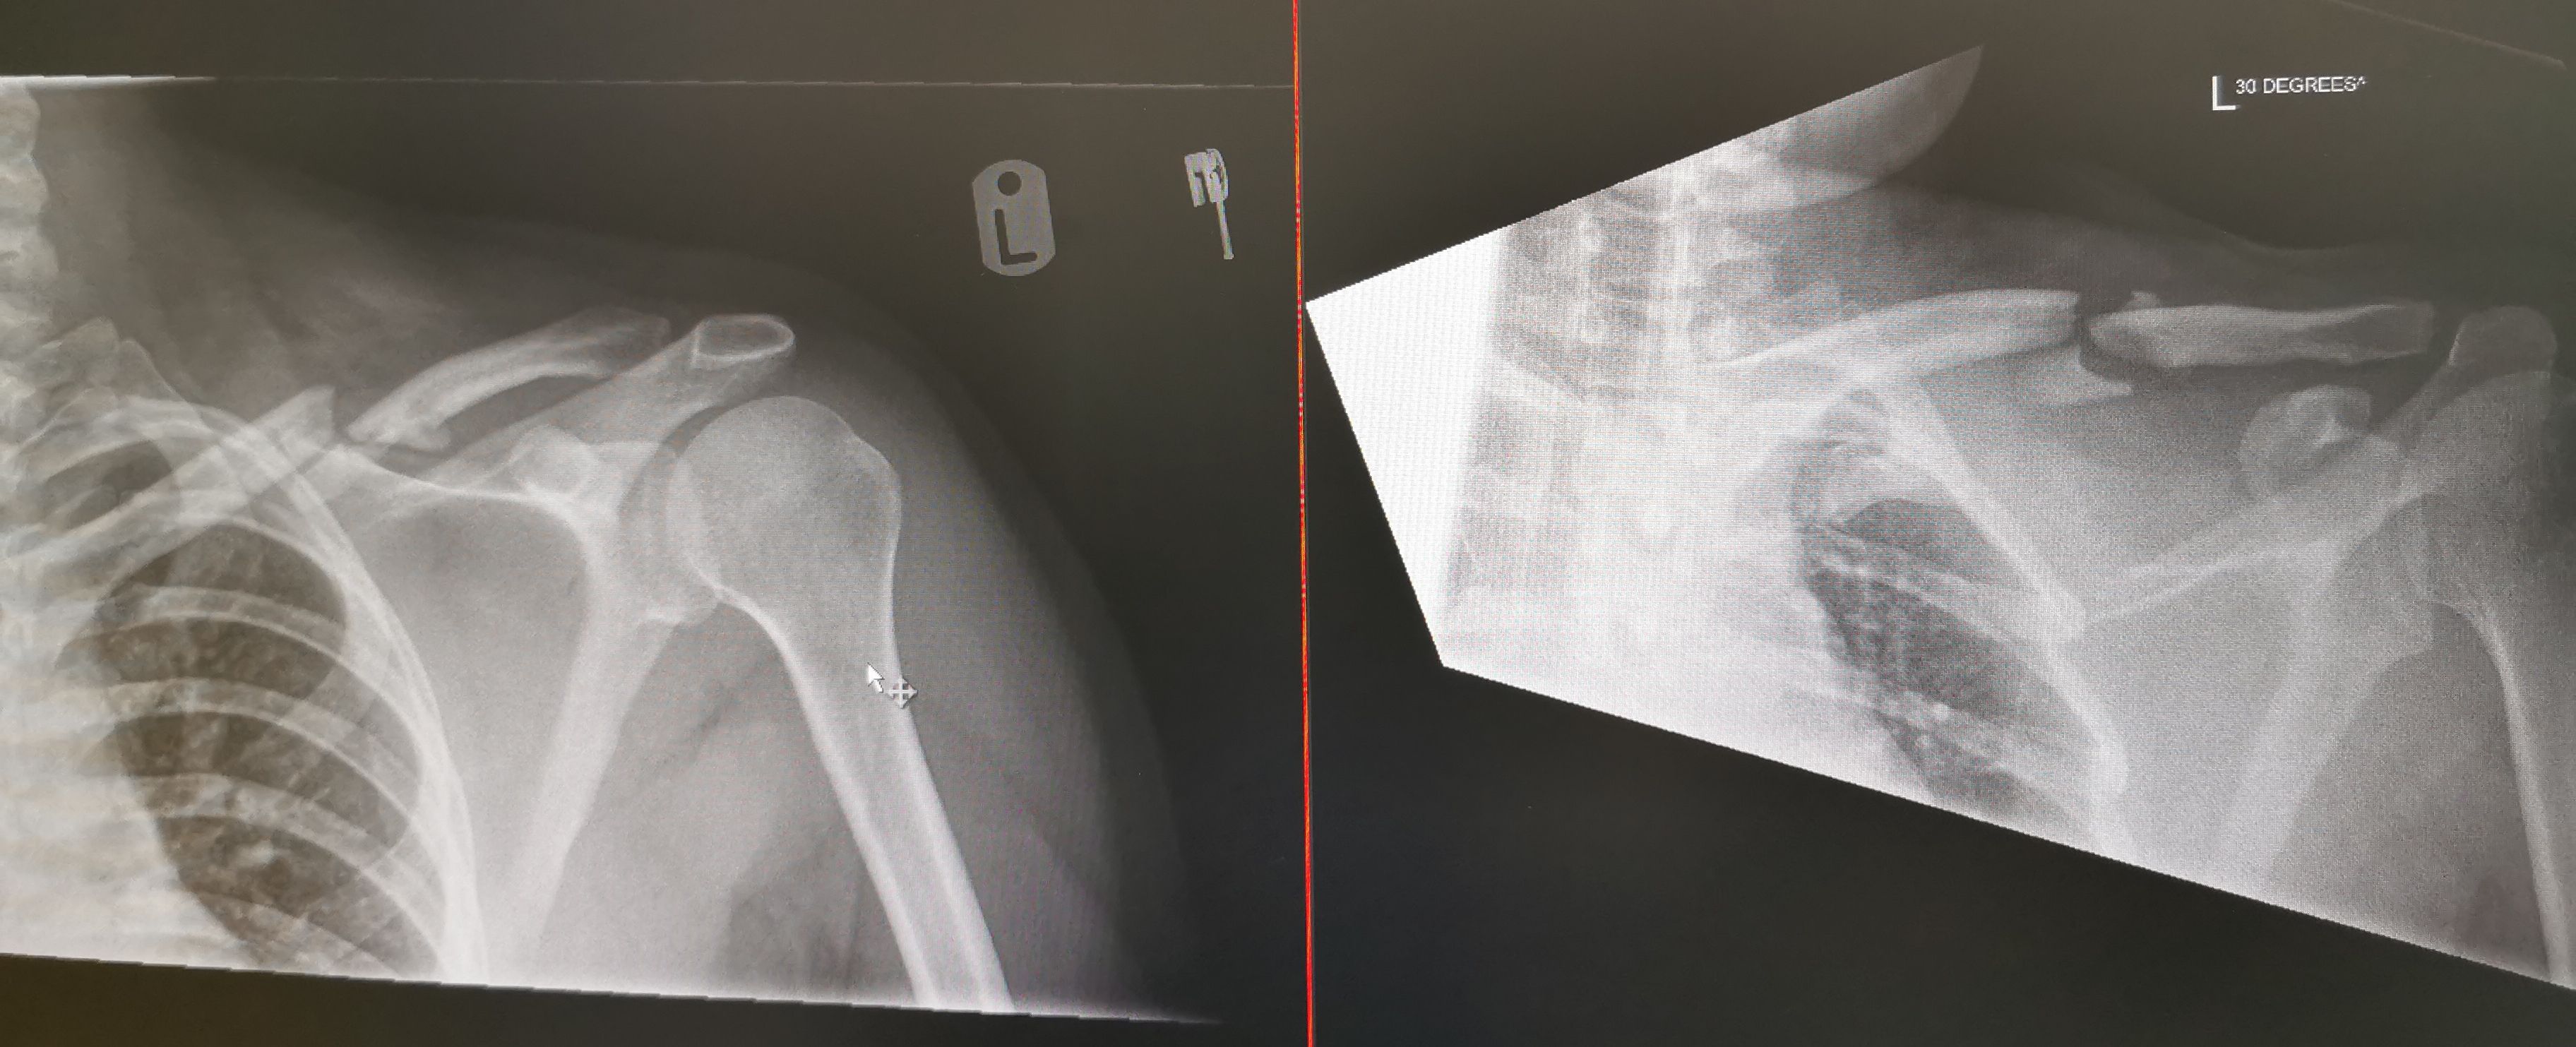

I broke mine in 2 places about 2.5 weeks ago now, cycling accident. The xray was from a couple of hours after. Had an appointment with fractures and orthopaedic clinic this week and the chap I saw was very non committal about fixing it or letting it heal. Anybody any thoughts about letting it heal or go for the surgery option?

My untrained eye struggles to see how it sorts itself out without future possible niggles, but I'm not an expert in these things.

As an aside, I'm grateful for my helmet doing it's intended job, as I don't think I'd be here without it